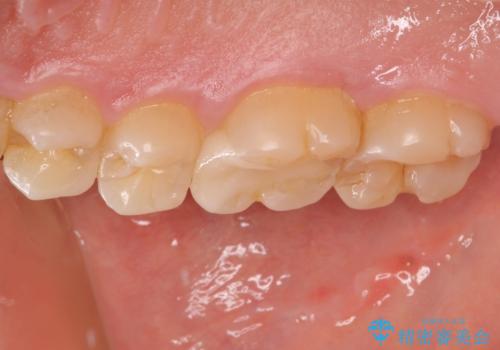

- 保険診療で治療した銀歯のやり替え希望の患者様です。

銀歯とその下の虫歯を除去し、形を整え、精度の良いシリコーンによる型どりを行いました。